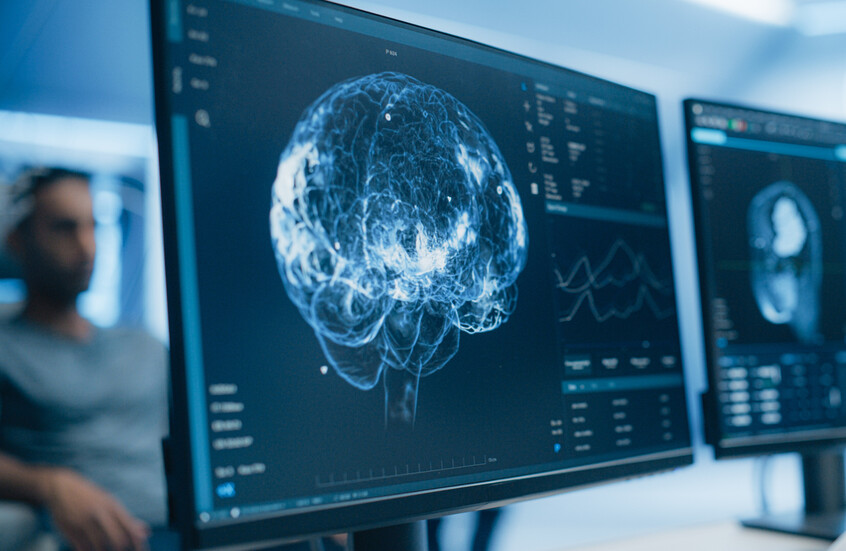

ما هي علامات الإصابة بسرطان الغدة الدرقية وهل يمكن علاج المرض؟

يعد سرطان الغدة الدرقية نوعا نادرا من السرطانات، ويؤثر على الغدة الدرقية، وهي غدة صغيرة في قاعدة العنق تنتج الهرمونات وتلعب دورا في التمثيل الغذائي والنمو والتطور.

ويعرف أن هذا النوع من السرطان شائع بين الأشخاص في الثلاثينيات من العمر والذين تزيد أعمارهم عن 60 عاما، كما أن النساء أكثر عرضة للإصابة به مرتين إلى ثلاث مرات أكثر من الرجال.

ويتمثل العارض الرئيسي لسرطان الغدة الدرقية في وجود كتلة في مقدمة العنق تكون عادة غير مؤلمة أو منتفخة.

وإذا وجدت تورما في رقبتك، فلا داعي للذعر لأن كتلة واحدة فقط من بين كل 20 كتلة في الرقبة يمكن أن تكون سرطانية.

والكتل في الرقبة شائعة وغالبا ما تكون أقل خطورة، ولكن إذا كانت التكتل صلبة، ولا تتحرك بسهولة ويبدو أنها تكبر بمرور الوقت، فمن المرجح أن تكون سرطانا.

ويقول موقع هيئة الخدمات الصحية الوطنية البريطانية (NHS) إنه يجب عليك زيارة طبيب عام إذا كان لديك أي تورم في مقدمة عنقك على الرغم من أنه من غير المحتمل أن يكون سرطانا.

وقد تصاحب الورم أعراض أخرى، بما في ذلك تورم الغدد، وبحة في الصوت، والتهاب الحلق، وألم في الرقبة، وصعوبة في البلع، وصعوبة في التنفس، وأحيانا إسهال واحمرار.

ويحدث سرطان الغدة الدرقية عندما يكون هناك تغيير في الحمض النووي داخل خلايا الغدة الدرقية وتبدأ في النمو دون حسيب ولا رقيب وتنتج كتلة.

ومن الصعب معرفة سبب هذا التغيير، ولكن هناك القليل منها يمكن أن يزيد من خطر حدوث هذا التغيير مثل أمراض الغدة الدرقية الأخرى، والتاريخ العائلي لسرطان الغدة الدرقية، والإشعاع، والسمنة، والورم الغدي العائلي.

ويمكن الوقاية من حالة واحدة تقريبا من كل 10 (9%) من الحالات، لذا من المهم تقليل المخاطر حيثما أمكن من خلال اتباع أسلوب حياة صحي وعدم التدخين.

هل يمكن علاج سرطان الغدة الدرقية؟

عادة ما يتم علاج سرطان الغدة الدرقية، ويمكن علاج العديد من الحالات بشكل كامل، وفقا لهيئة الخدمات الصحية الوطنية.

ومن بين جميع حالات سرطان الغدة الدرقية، يعيش 84% من سرطان الغدة الدرقية لمدة 10 سنوات أو أكثر.

وتشمل العلاجات الرئيسية لسرطان الغدة الدرقية الجراحة لإزالة جزء أو كل الغدة الدرقية، والعلاج باليود المشع، والعلاج الإشعاعي الخارجي والعلاج الكيميائي أو العلاجات المستهدفة.

وبمجرد الانتهاء من العلاج، من المهم حضور مواعيد المتابعة لأن سرطان الغدة الدرقية يمكن أن يعود في بعض الأحيان بعد العلاج.

وإذا تمت إزالة الغدة الدرقية كجزء من العلاج، فلن يعود بإمكان جسمك إنتاج هرمون الغدة الدرقية، وعادة ما يتناول هؤلاء الأشخاص حبوبا يومية تحتوي على هرمون الغدة الدرقية الاصطناعية لضمان عدم ظهور أعراض قصور الغدة الدرقية مثل التعب والحساسية تجاه البرد وزيادة الوزن والإمساك والاكتئاب وهشاشة الشعر والأظافر، بالإضافة إلى الحركات والأفكار البطيئة وآلام العضلات وتشنجاتها وضعفها وأكثر من ذلك.

ويمكن للناس أن يعيشوا حياة كاملة وطويلة دون الغدة الدرقية طالما أنهم يتناولون أدويتهم ويستمرون في مراجعة الطبيب بعد الجراحة.